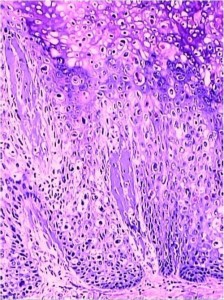

图5,猫鳞状细胞原位癌,也叫鲍温病(bowen disease)

鲍温病(附有病理)

皮肤病及病理学习鲍温病